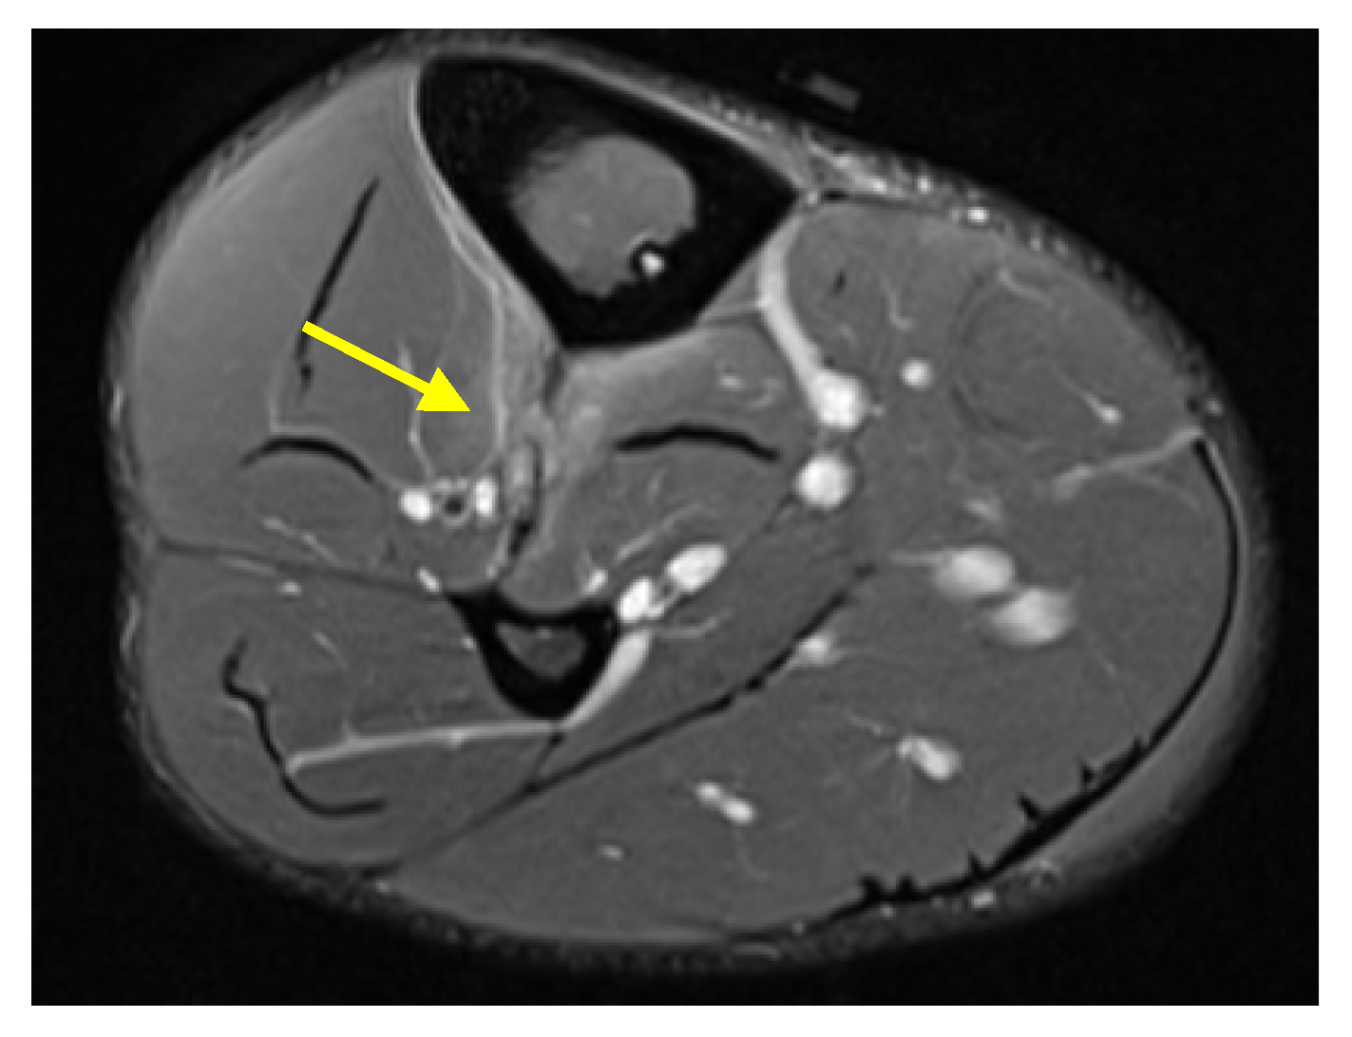

Case 5: A 23-year-old male collegiate alpine ski racer presented with acute right lower leg pain at the level of the boot-line after a crash. During the crash, the posterior portion of the ski broke and the patient felt the boot impact the posterior lower leg. Physical exam was notable for tenderness to palpation over the anterolateral lower leg at and immediately proximal to the boot-line. Radiography was unremarkable. MRI revealed a high-grade tear of the tibiofibular IOM 8 cm proximal to the tibial plafond, with 14 cm of craniocaudal extension and associated periosteal edema (Figure 3). He returned to the clinic two weeks after injury with 80–90% overall symptom improvement.

Figure 3. Case 5. (a) Axial proton density fat-saturated MR image of the mid tibia–fibula with focal IOM discontinuity and adjacent edema (yellow arrow). (b) Coronal short tau inversion recovery (STIR) MR image of both lower legs with associated fluid and edema adjacent to the disrupted right mid-IOM (yellow arrowhead).